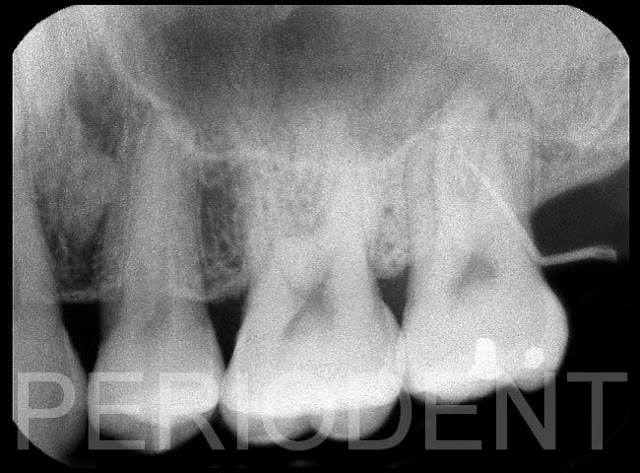

患者左上第二大臼齒顎側常常牙齦腫脹,經牙周探針測量有10mm深的囊袋

牙周手術翻開翻瓣後,見到Palatal Root有嚴重的牙結石堆積,及齒槽骨破壞

清除牙結石及發炎組織後,發現根尖懸浮在骨缺損內,且可見到鼻竇膜